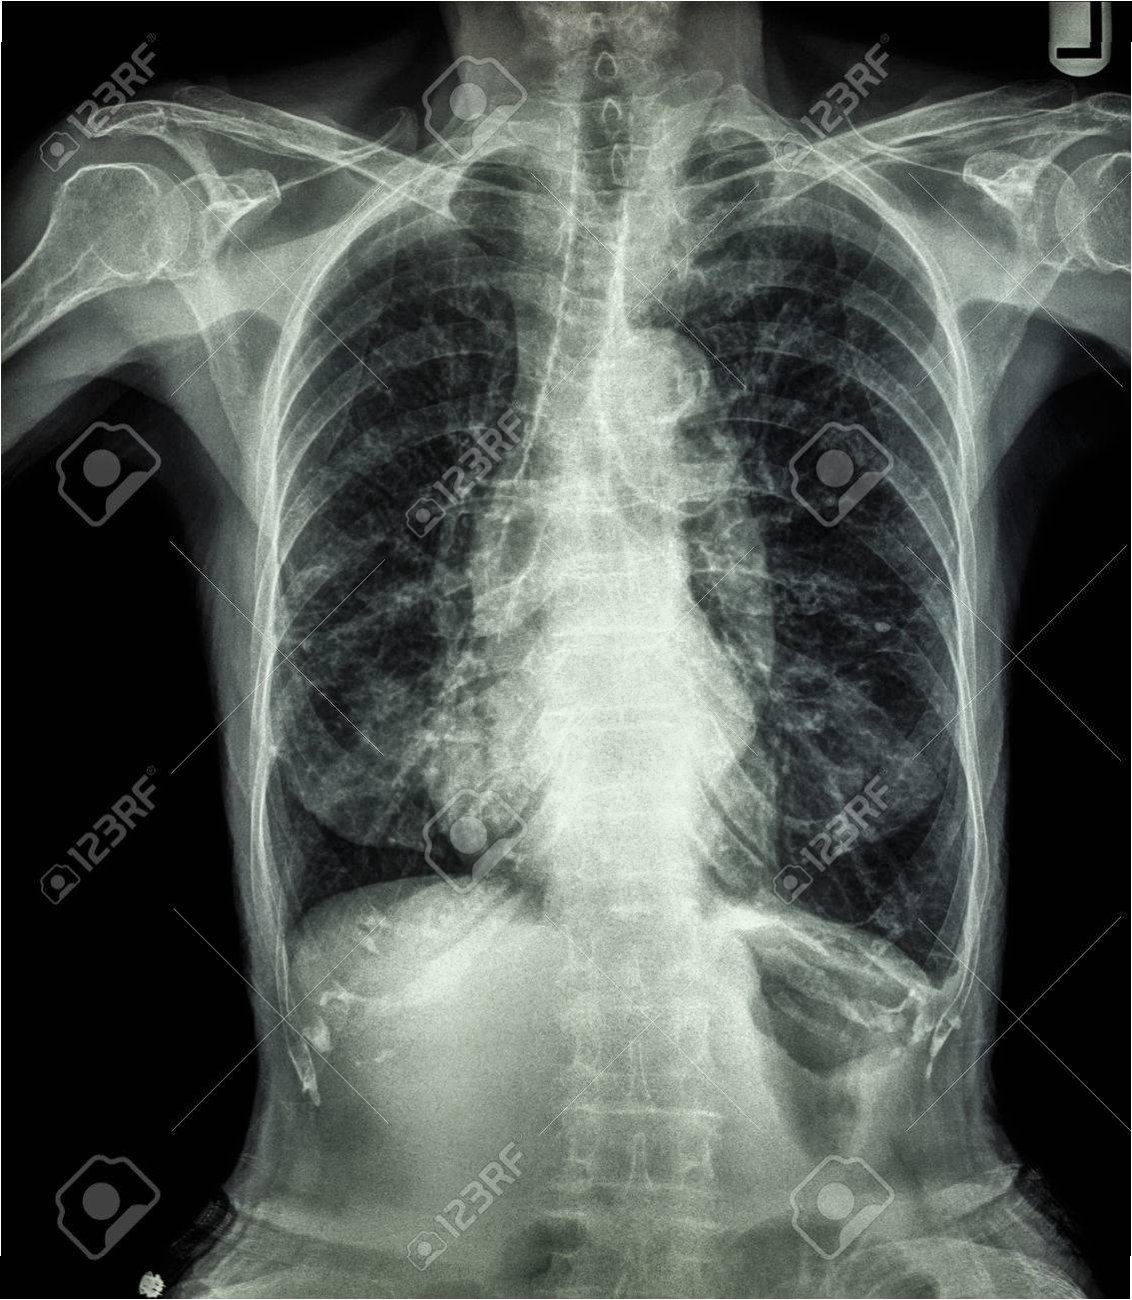

2019년부터 시작된 원인 불명의 밤마다 반복되는 고열로 병원을 찾은 사이먼스 씨는 CT 검사 결과 충격적인 사실을 마주했습니다. 사고 당시 폐 깊숙이 들어간 먼지 파편이 체외로 배출되지 못한 채 딱딱하게 굳어 왼쪽 폐 기관지를 완전히 막고 있었던 것입니다. 그는 “기계에 깔려 움직일 수 없을 때 먼지를 들이마셨는데, 그게 깊이 들어가 굳어버렸다”고 당시 상황을 설명했습니다. 의료진은 외상으로 인해 체내에 남은 이물질이 장기간에 걸쳐 칼슘으로 둘러싸여 석회화가 진행된 것으로 판단했습니다. 정밀 검사 결과, 좌측 폐는 5년간의 감염으로 기능을 완전히 상실한 상태였습니다.

의료진은 처음에는 석회화된 부분만 제거하려 했으나, 손상 범위가 너무 넓어 폐 전체를 적출해야 한다는 결론에 이르렀습니다. 사이먼스 씨는 결국 왼쪽 폐를 떼어내는 수술을 받았습니다. 그는 “작은 먼지 한 톨이 내 인생을 이렇게 바꿀 줄 몰랐다”며 “수술 동의서에 서명하던 순간이 인생에서 가장 무거웠다”고 심경을 토로했습니다. 이처럼 외상으로 체내에 남은 이물질은 장기간에 걸쳐 석회화되며 염증이나 조직 괴사를 일으킬 수 있습니다. 특히 폐 조직은 통증 수용체가 적어 초기 증상 인지가 어렵고, 뒤늦게 발견되는 경우가 많아 주의가 필요합니다.

전문가들은 외상으로 인해 유리 조각이나 금속 파편 같은 이물질이 체내에 남을 경우, 장기간에 걸쳐 석회화가 진행되면서 염증이나 조직 괴사를 일으킬 수 있다고 경고합니다. 특히 폐 조직에는 통증 수용체가 거의 없어 초기에는 증상을 느끼기 어렵다가 뒤늦게 검진을 통해 발견되는 경우가 많습니다. 염증이 심해져 늑막이나 기관지를 자극하면 발열, 기침, 호흡곤란 등의 증상이 나타날 수 있으므로, 폐 건강에 대한 각별한 주의가 요구됩니다. 작은 이물질이라도 방치하면 심각한 결과를 초래할 수 있음을 사이먼스 씨의 사례는 명확히 보여줍니다.